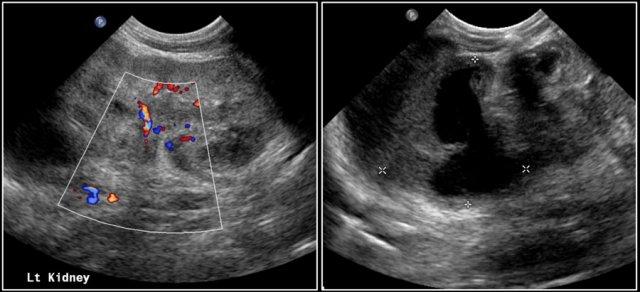

Đây là hình ảnh của một bé gái 1,5 tuổi có khối u sờ thấy được ở bụng trái.

Siêu âm cho thấy một khối u lớn cấu thành bởi vô số nang, xuất phát từ thận trái.

Trên ảnh MRI mặt phẳng trán chuỗi xung T2W, các nang được hiển thị rõ ràng.

Phần còn lại của thận trái nằm ở phía đuôi của khối u.

Kết quả giải phẫu bệnh xác định là u nguyên bào thận dạng nang biệt hóa một phần.